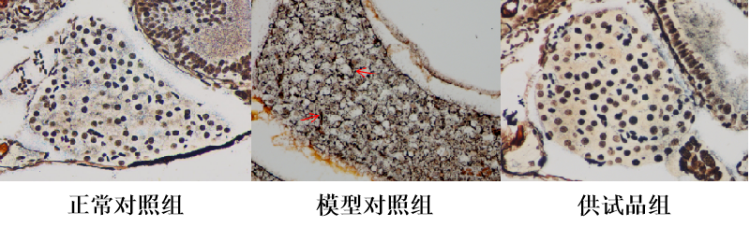

图1. 斑马鱼肝脏脂肪染色强度表型图

(网状纤维着黑色,胶原纤维着黄或黄褐色,细胞核着褐或黑褐色,红色箭头指向网状纤维)

从实验结果可以看到,服用供试品组斑马鱼肝纤维化较模型对照组显著改善。